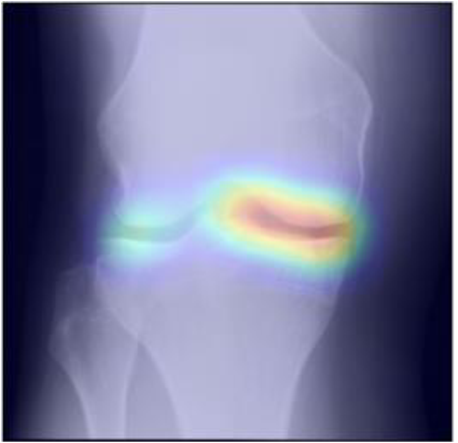

While machine learning-based approaches yield stronger prediction than conventional statistical models, (e.g. LR), they are less transparent, which can lead to lack of trust from clinicians. To address this drawback, various methods have been developed to explain the decisions of ”black-box systems” [24, 26, 27]. As such, we utilized the GradCAM approach [24] that allowed us generating an attention map, in order to highlight the zones where the CNN has paid its attention. While being attractive, this approach can also lead to wrong interpretations, i.e. there is no theoretical guarantee that the neural network identifies causal relationships between image features and the output variable. Therefore, a thorough analysis of the attention maps is required to assess the significance of certain features and anatomical zones picked-up by the model. Such analysis, however, could enable new possibilities for investigation of the visual features. For example, we observed interesting associations in the GradCAM-generated attention maps (Figure 5), some of which are not captured by KL grading. As such, tibial spines (previously associated with OA progression [28]) were highlighted in multiple attention maps. These associations, however, do not hold for all the progressors.

Figure 4: Examples of GradCAM-based attention maps for the knees having osteoarthritis at baseline and progressed in the future. Fine-grained sub-types of progression are also specified. The presented images are of 140×140140140140\times 140 mm.